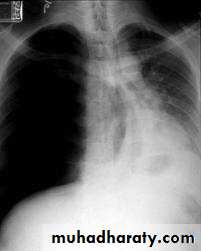

Tension pneumothorax is due to unidirectional flow of air into the pleural space from which it cannot escape. It develops when intrapleural pressure > atmospheric pressure during expiration, causing collapse of the involved lung, shift of the mediastinum, and potentially acute deterioration in cardiopulmonary status requiring prompt relief of the positive pleural pressure.List the physical findings that suggest tension pneumothorax

#Chest tube insertion has been recommended for patients with primary SP who failed observation and simple aspiration and for all patients with secondary SP. # In tension pneumothorax . the mediastinal contents, including the heart, are shifted to one side. Treatment consists of emergent needle decompression repeated spontaneous pneumothorax should be treated by pleurodesis or surgical intervention (including parietal pleurectomy)